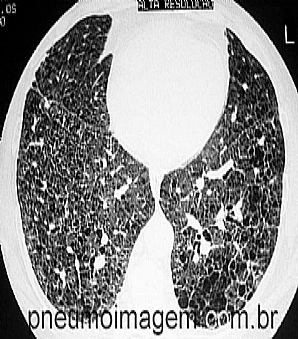

FAÇA O DOWNLOAD SOBRE AS ORIENTAÇÕES DA ATS AO PACIENTE COM FIBROSE PULMONAR.A ATS desenvolveu um folheto para educação do paciente sobre a fibrose pulmonar idiopática que descreve como a doença lesa os pulmões, os sintomas, o diagnóstico e as estratégias de tratamento, incluindo o transplante de pulmão. O folheto está disponível para download gratuitamente, basta clicar aqui.